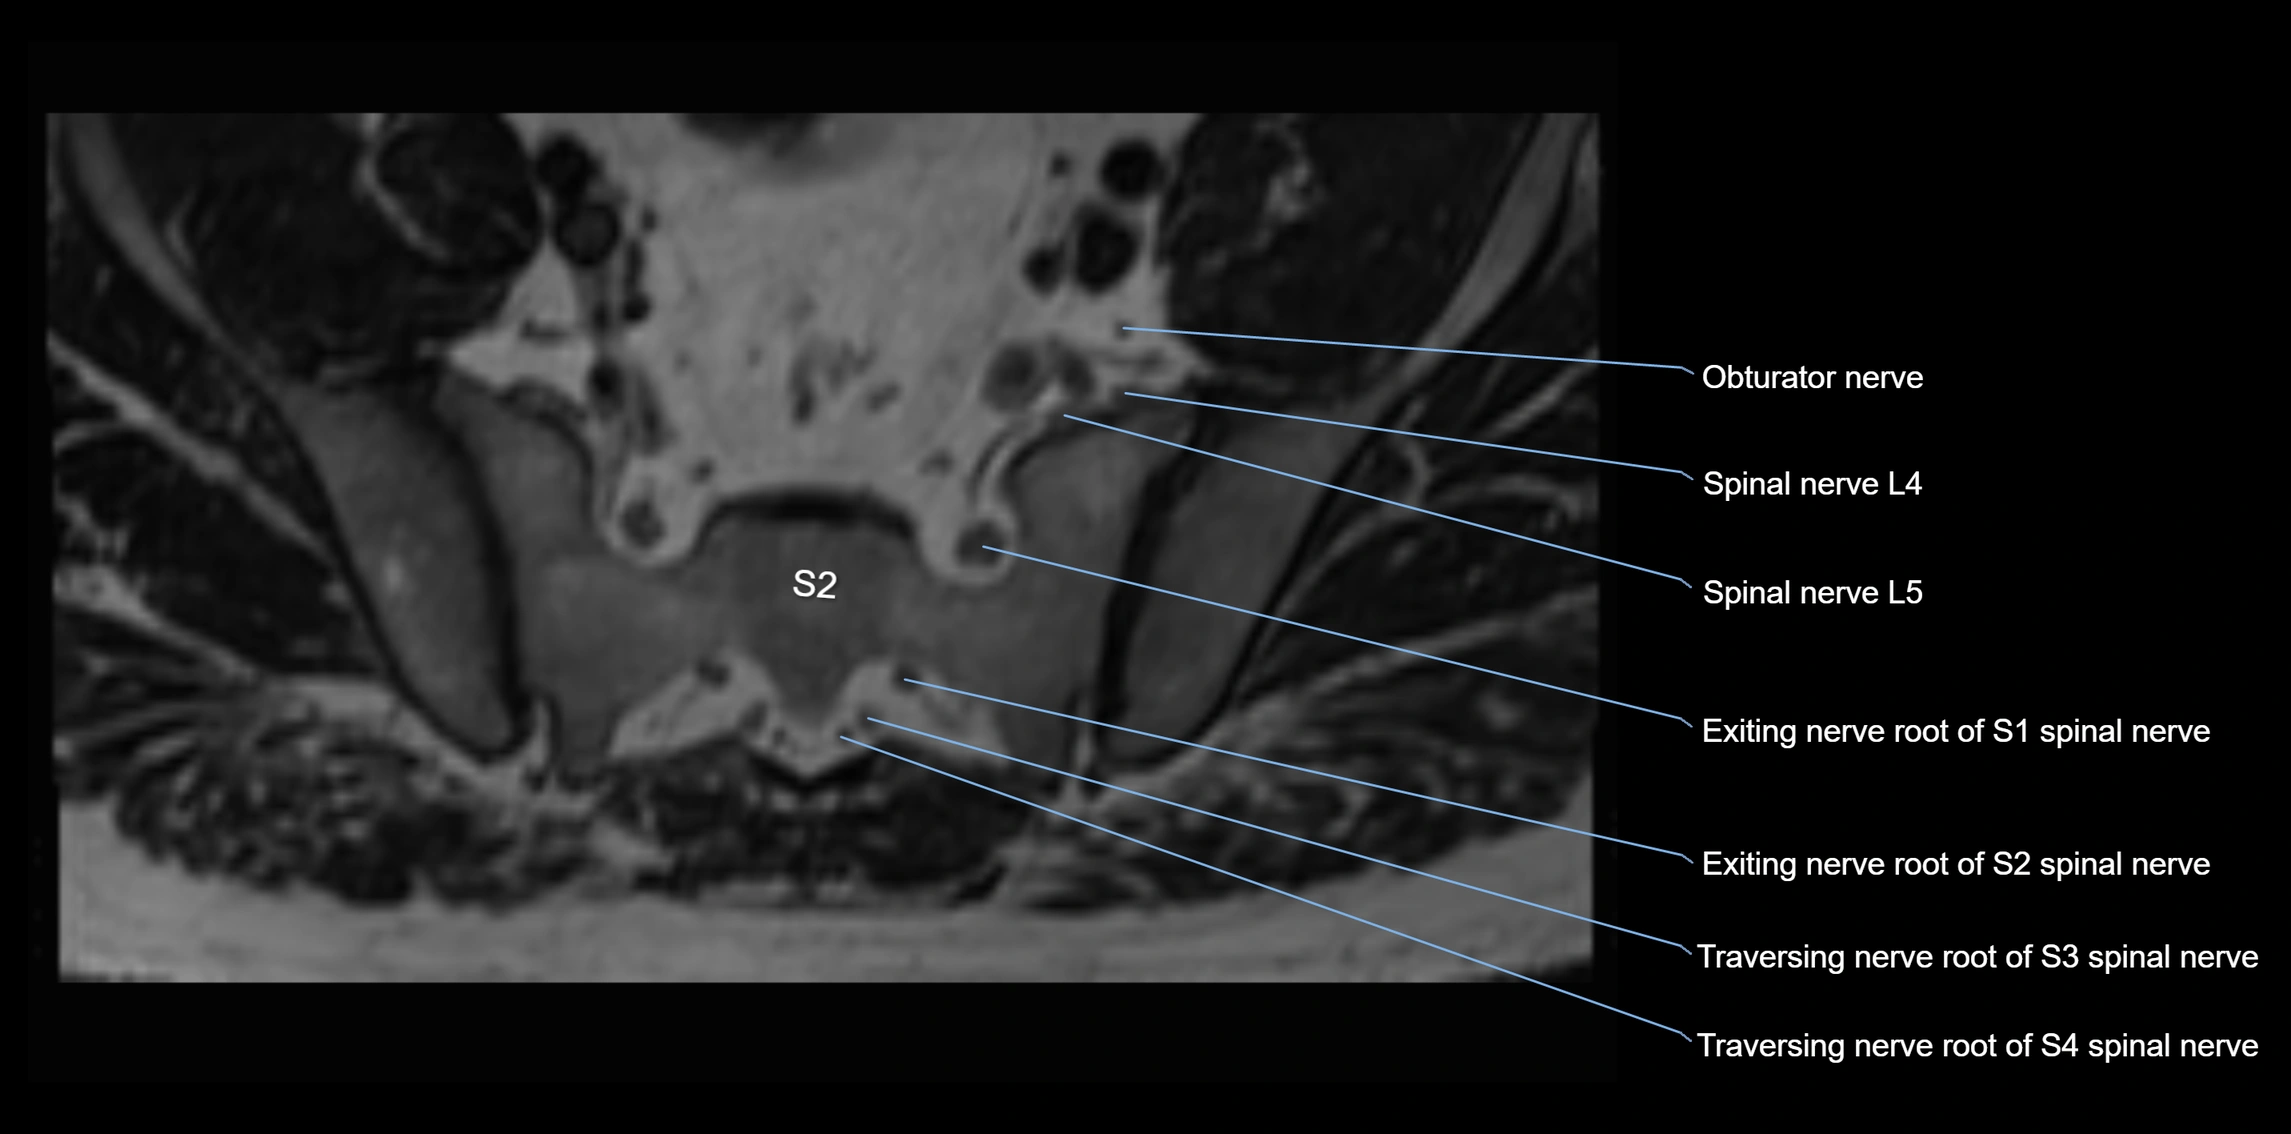

MRI image

image